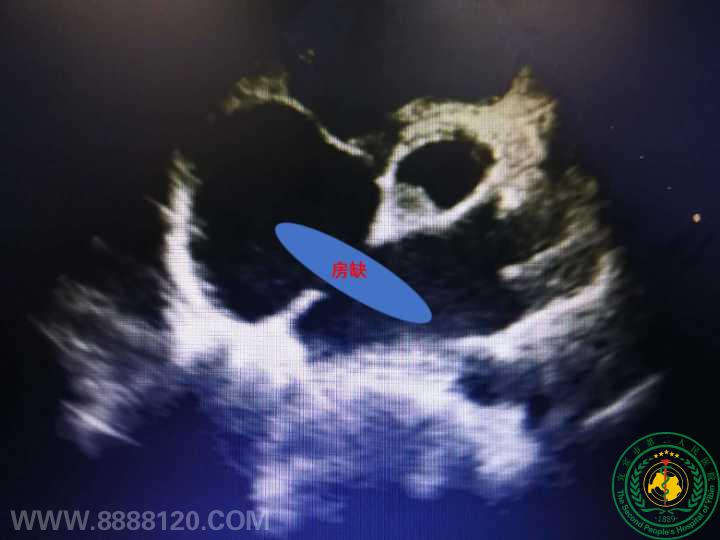

宜宾首例超声引导经胸房缺封堵术在我院成功开展

宜宾首例超声引导经胸房缺封堵术在我院成功开展16940